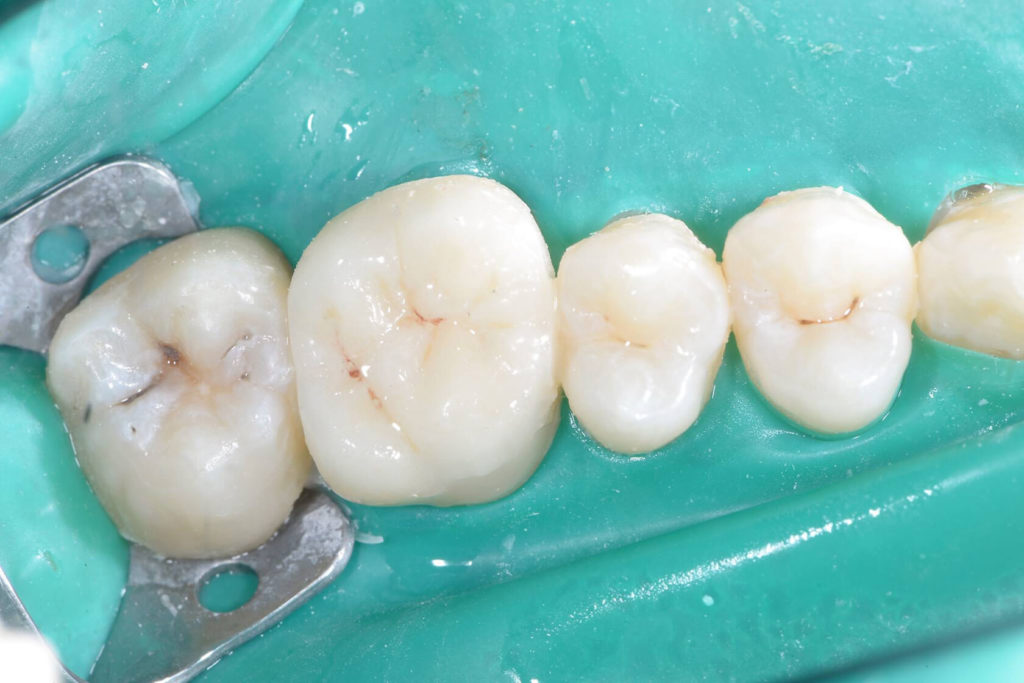

Patient presented with deep distal decay on first molar. Used deep margin elevation and papillectomy. No attempt was made to establish 3 mm biologic width space. Overlay prep and lithium disilicate indirect restoration placed. Photos from 15 month follow up included.